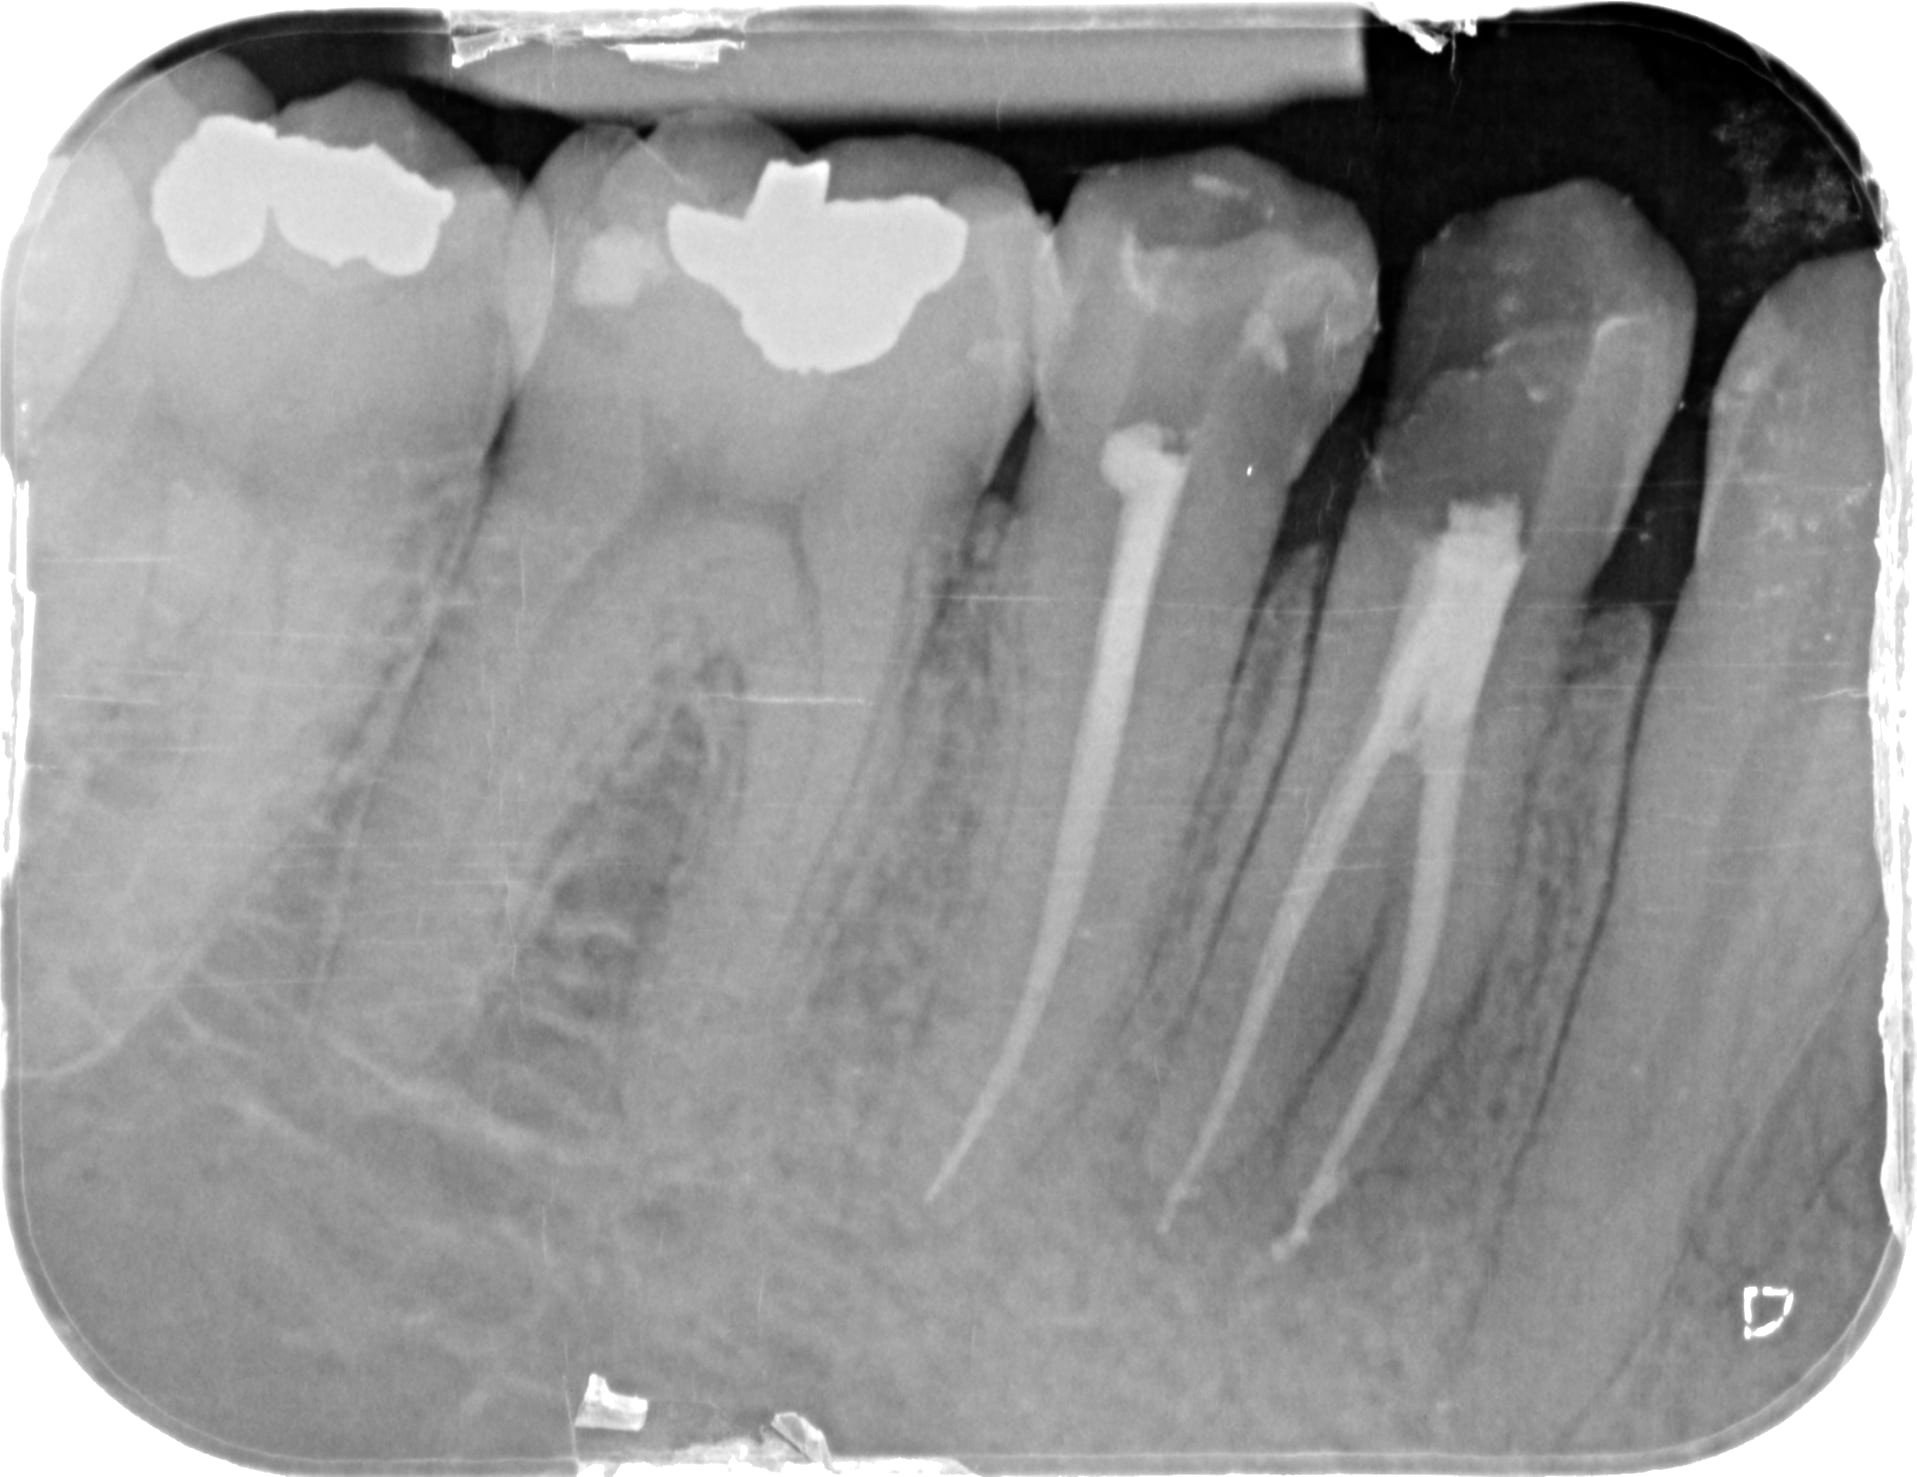

Il y aurait une épidémie ? J'ai eu la même cet après-midi.

Zyz3djm011to8hmuddi8u171u90l - Eugenol

1osff7kk16ybclkejie7yhaqia0r - Eugenol

Que de radios ! Tu devrais investir dans un localisateur d’apex ☝️